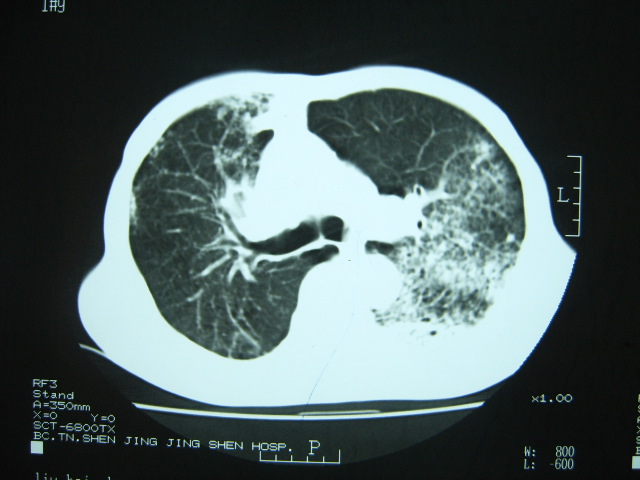

男74岁,咳嗽,寒战,低烧。有糖尿病史。

两肺结核,空洞形成,左下肺肺段隔离症待排

1、左下肺肺脓肿,合并霉菌球形成?.2、双肺陈旧性病灶.3、右上肺病灶警惕瘢痕癌,建议定期复查.

两肺结核,左下肺空洞性病变,结核性?炎性?癌性?抗炎治疗后复查。

两肺结核,左下肺大片实变,内见空洞性病变,壁不规则,结合糖尿病史,考虑:结核性?霉菌性?建议结合实验室检查或治疗后复查。